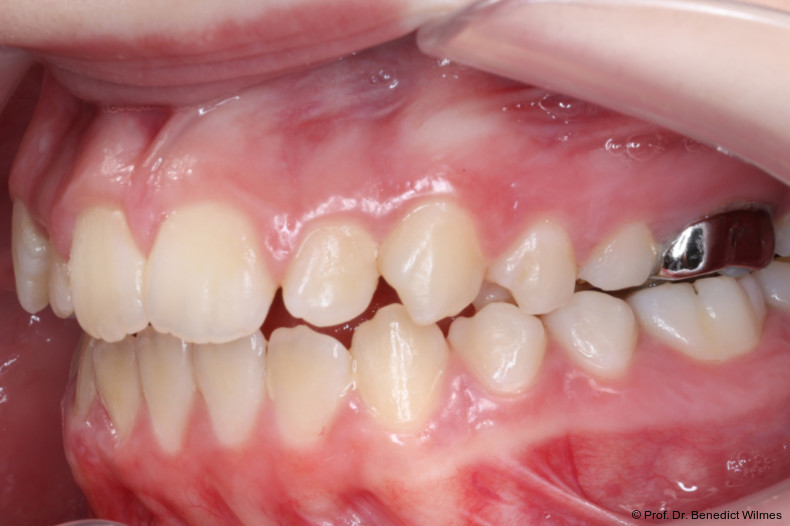

Eine 13-jährige Patientin stellte sich mit beidseitigem Kreuzbiss, einem anterioren offenen Biss und einer Angle Klasse II vor. Das viszerale Schluckmuster wurde mittels logopädischer Maßnahmen umgestellt, der offene Biss persistierte jedoch (Abb. 3a–l).